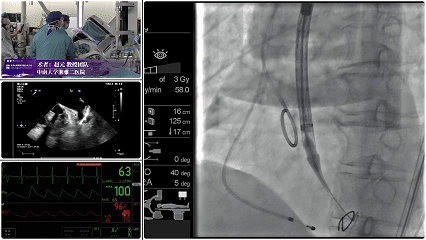

Step 5.最终造影:位置合适,瓣膜形态良好,无瓣周漏。

患者压差由105mmHg降至17mmHg。

该环上瓣采用独特的平衡收腰结构,在适配极小瓣环的同时,实现了锚定稳定性与血流动力学的双重优化。针对患者极小瓣环的特点,选择AV23规格瓣膜。术后超声显示,患者跨瓣压差由术前105mmHg 骤降至17mmHg,血流动力学显著改善,无瓣周漏。

手术过程与术后转归